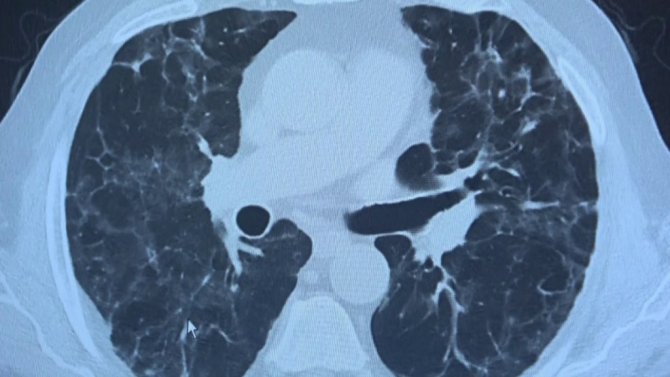

Korona virüs hastalığını atlatmış kişiler belli bir zaman geçtikten sonra halsizlik, nefes darlığı, enerjisi bitmiş şekilde tekrar kliniklere başvuru yapıyor. Uzmanların "uzamış Covid" ve "post Covid" dedikleri bu durum hem hastaların hem de hasta yakınlarının yaşam kalitesini olumsuz etkiliyor. Bu kapsamda 10 binin üzerinde Covid-19 hastası tedavi eden VM Medical Park Samsun Hastanesi'nde görevli Göğüs Hastalıkları Uzm. Prof. Dr. Şevket Özkaya ve Dr. Yağmur Sarıtaş klinikte karşılaştıkları yeni bir durumla ilgili bilgi verdi. Prof. Dr. Şevket Özkaya, Covid-19 geçirmiş ve tekrar farklı şikayetlerle kendisine başvuru yapmış hastaların akciğerlerini inceledi. Hastaların akciğerlerinde sekel lezyon denilen lekelerin görülmeye devam ettiğini belirtti.

Kliniğe gelen kişilerin akciğer tomografilerine inceleyen Prof. Dr. Özkaya, "62 yaşında bir teyzemiz 11 Mart'ta yoğun bakımda solunum yetmezliği ile hastaneye yattığında hayati tehlikesi vardı ve Covid- 19'u atlattı. Yalnız aradan 3 ay geçmesine rağmen hala akciğerinde Covid - 19'un uzamış etkileri dediğimiz sekel lezyonları var. Bu hasta nefes darlığı çekiyor. Diğer bir vaka örneği verirsek, 62 yaşında bir erkek hasta. Mart'ın sonlarında geldiğinde röntgeninde küçücük buzlu camları vardı. Birden Nisan'ın ilk haftası 10 gün içinde çok yaygın lezyonlar olmaya başladı. Yoğun bakımda takip etmek zorunda kaldık. Bu hastamızın hayatı kurtulduktan sonra filmine baktığımızda yine sekel lezyonlar görüyoruz. Böyle yıpratıcı, harap edici bir klinik tablo ortaya çıkıyor" diye konuştu.